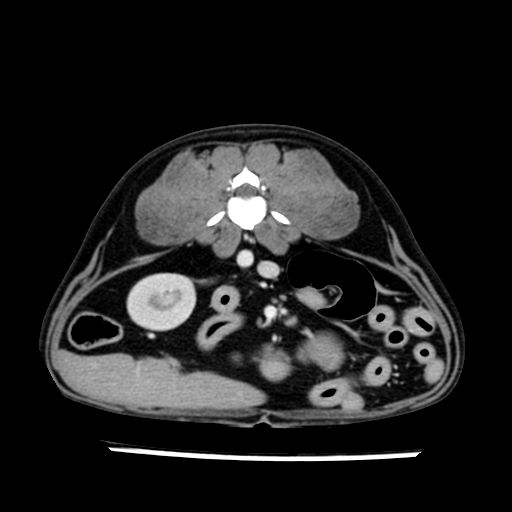

prescritto esame TAC

sequenza immagini limitata al fegato reni e surreni

le immagini ecografiche rispetto alla tac datano circa 7 mesi prima ,le surrenali sono normali nonostante il test acth sia risultato positivo .all’esame TAC dopo diversi mesi risultano aumentate armonicamente nel volume e si individua un forte sospetto di adenoma ipofisario .

sospetto adenoma ipofisario vs. meno probabilmente meningioma della base; intertiziopatia polmonare; lesione espansiva epatica, verosimilmente del lobo laterale sinistro, di sospetta natura neoplastica; lesioni spleniche di natura da definire; iperplasia/ipertrofia delle ghiandole surrenali, bilateralmente; vertebra di transizione del rachide toracico; tenosinovite cronica del muscolo bicipite brachiale di destra.